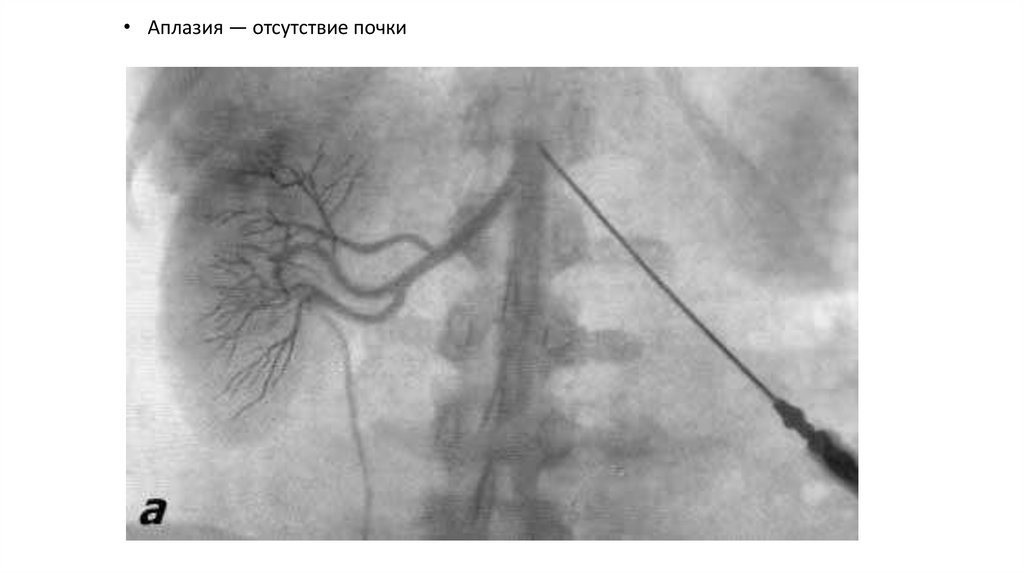

• Аплазия — отсутствие почки